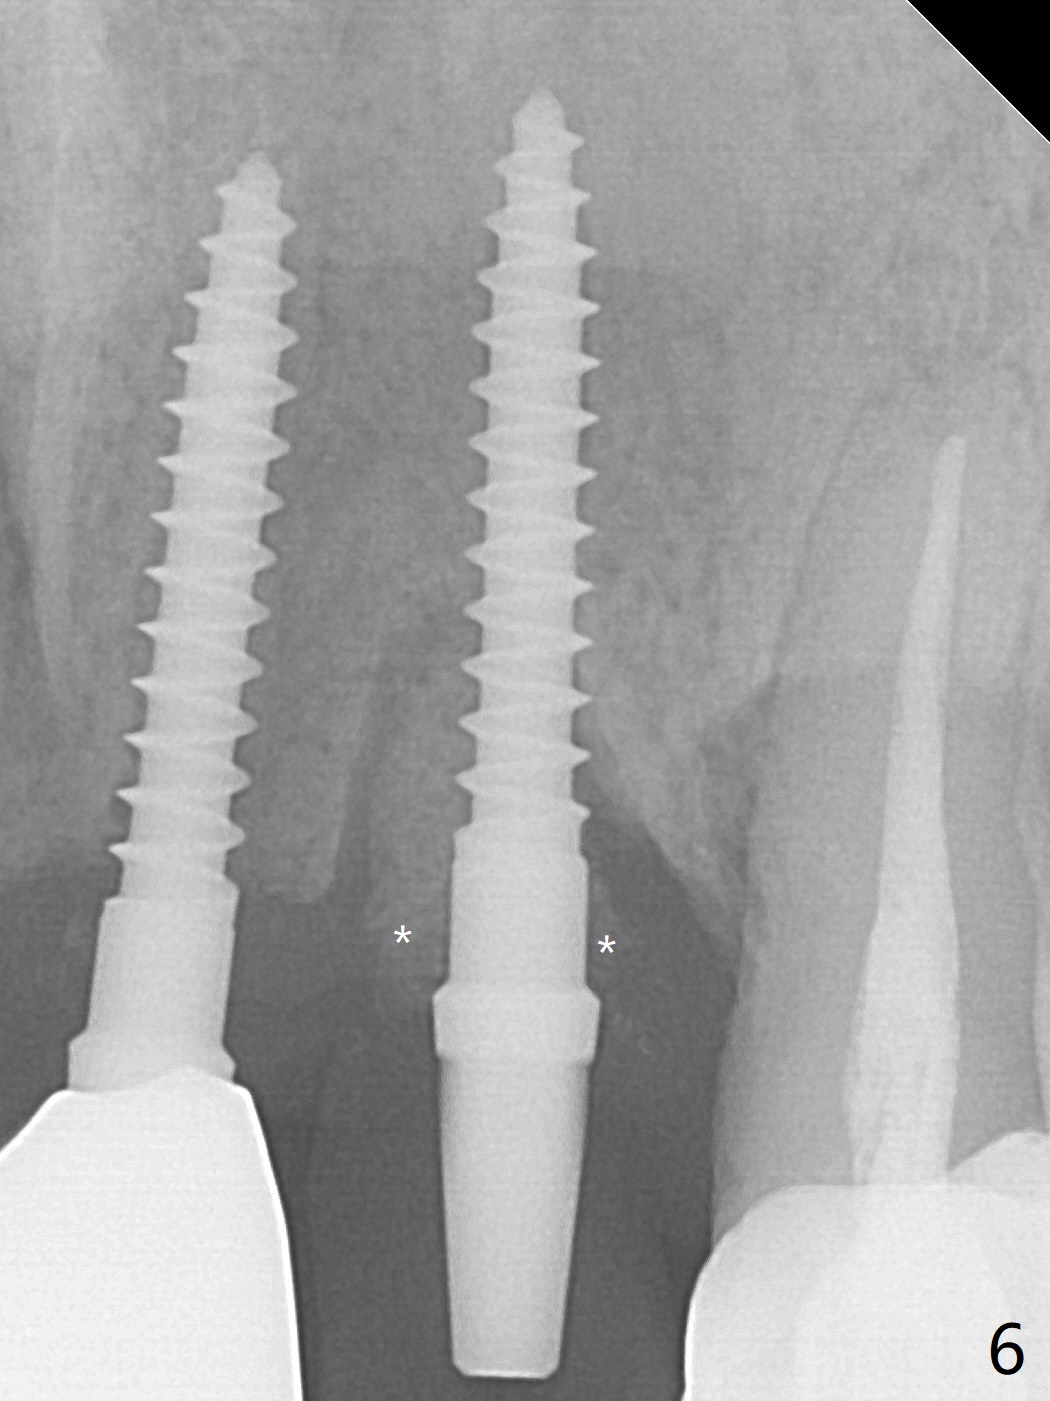

The tooth #10 has severe gingival recession (Fig.1) with loss of the buccal plate (Fig.2 *). After the initial osteotomy depth (Fig.3) increases by 2 mm, a 2.5x14(2) mm 1-piece implant is placed with insertion torque >60 Ncm (Fig.4). Palpation indicates the native bone apparently wider than CT shows. There is no sign of buccal or palatal plate perforation by palpation during osteotomy or implant placement. Vera Graft is placed repeatedly around the coronal threads (Fig.5-7 *). An immediate provisional is fabricated to close the socket (Fig.8). The buccal plate appears to collapse 1 month postop (cortical plate graft apparently more appropriate in this case); the margin of the provisional is trimmed so that the gingiva may grow incisally (Fig.9). The provisional dislodges several times postop due to short abutment. By nearly 4 months postop, the coronal bony defect seems to have been repaired (Fig.10 *). The tooth #11 has tenderness with bone loss (Fig.10 ^), corroborated by CT (distal bone loss, Fig.11 *). Since the apical bone is narrow (Fig.12), a narrow long implant is expected (Fig.13). Use an implant (3.5x13 mm) consistent with those at #14 and 15.